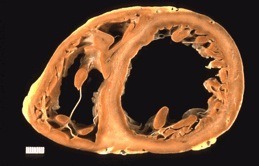

Alteraciones macroscópicas:

- El corazón suele estar agrandado, pesa más y tiene una consistencia blanda, debido a la dilatación de todas las cavidades.

- Los trombos parietales son frecuentes y son una fuente posible de émbolos.

- No existen alteraciones valvulares primarias, y cuando hay insuficiencia mitral (o tricuspídea), se relaciona con la dilatación sufrida por la cavidad ventricular.